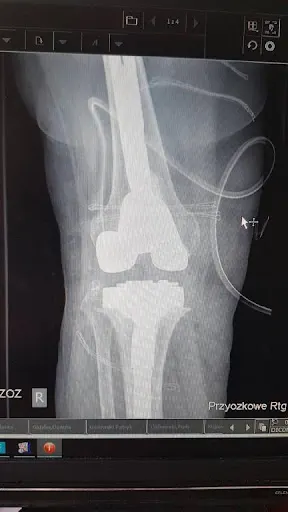

### Orthos – ortopedia w Gdyni W Gdyni, przy adresie 81-525, działa Orthos – przychodnia ortopedyczna specjalizująca się w diagnostyce i leczeniu schorzeń układu ruchu. Prowadzi ją dr n. med. Tomasz Grudniewski, doświadczony ortopeda i chirurg, który zdobył uznanie pacjentów dzięki profesjonalnemu podejściu. Na Google firma zbiera ocenę 4.3/5 na podstawie 6 opinii, co odzwierciedla solidną reputację w lokalnej społeczności. Pacjenci podkreślają fachowość wizyt, w tym szczegółowe wyjaśnienia i cierpliwość lekarza, szczególnie wobec dzieci. Przykłady obejmują udane operacje biodra, po których pacjenci szybko wracali do sprawności – jeden z nich chodził bez kul po półtora miesiąca, planując drugą procedurę. Inni chwalą pomoc pooperacyjną, np. przy rekonwalescencji kolana, gdzie dr Grudniewski przeprowadził dokładny wywiad, badanie i udzielił jasnych wskazówek. Leczenie przewlekłych chorób, jak łuszczycowe zapalenie stawów, też spotyka się z uznaniem za empatię i skuteczność. Mimo pojedynczej negatywnej opinii, większość klientów poleca Orthos za skupienie na pacjencie i rzetelną opiekę. To miejsce, gdzie mieszkańcy Gdyni i okolic znajdują wsparcie w problemach ortopedycznych. (Słowa: 198)